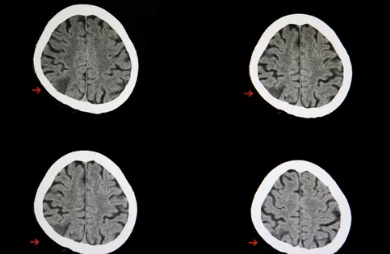

- 뇌졸중: 뇌혈관이 막히거나 터져 발생하는 질환입니다. 갑작스러운 hemiplegia, 언어 장애, 의식 상실 등이 나타납니다.